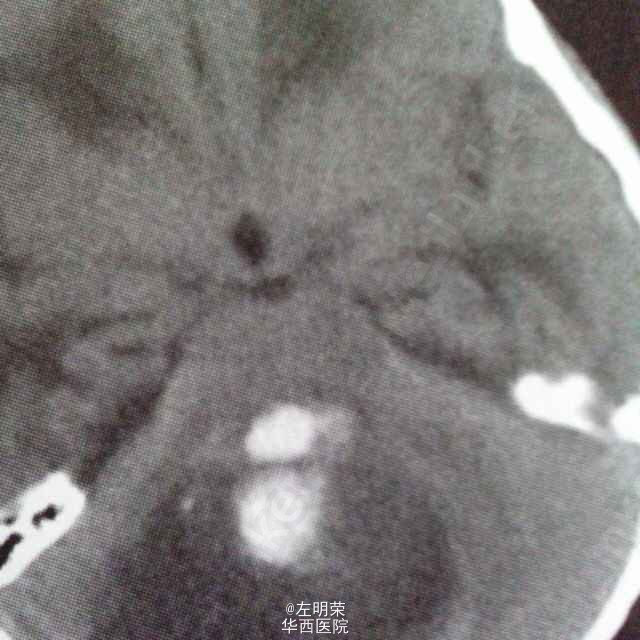

女孩,10岁,以阵发性头痛伴呕吐2月余,加重伴视力下降10余天入院;MRI特点:于小脑半球内巨大囊实性不均匀强化团块,占位周边无明显水肿,小脑扁桃体下疝,四脑室受压变形,可考虑为星形细胞瘤;因为毛细胞型星形细胞瘤是儿童常见的胶质瘤,最常见于小脑半球-小脑蚓部,多表现为较大的类圆形囊性病灶伴有壁结节或较大的类圆形实性肿块伴较大坏死区,本例囊内部分经CT证实为出血,提示肿瘤可能存在恶性进展可能,故应考虑高级别星形细胞瘤可能。鉴别:髓母细胞瘤,血管内网状细胞瘤,转移瘤。术后病理:星形细胞瘤伴大片坏死(WHO-III级)